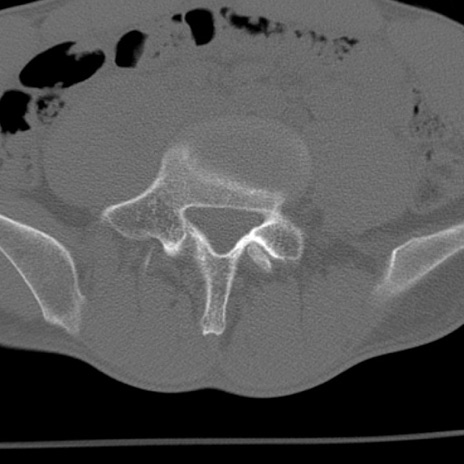

症例3 腰椎CT(横断像)

腰椎CT